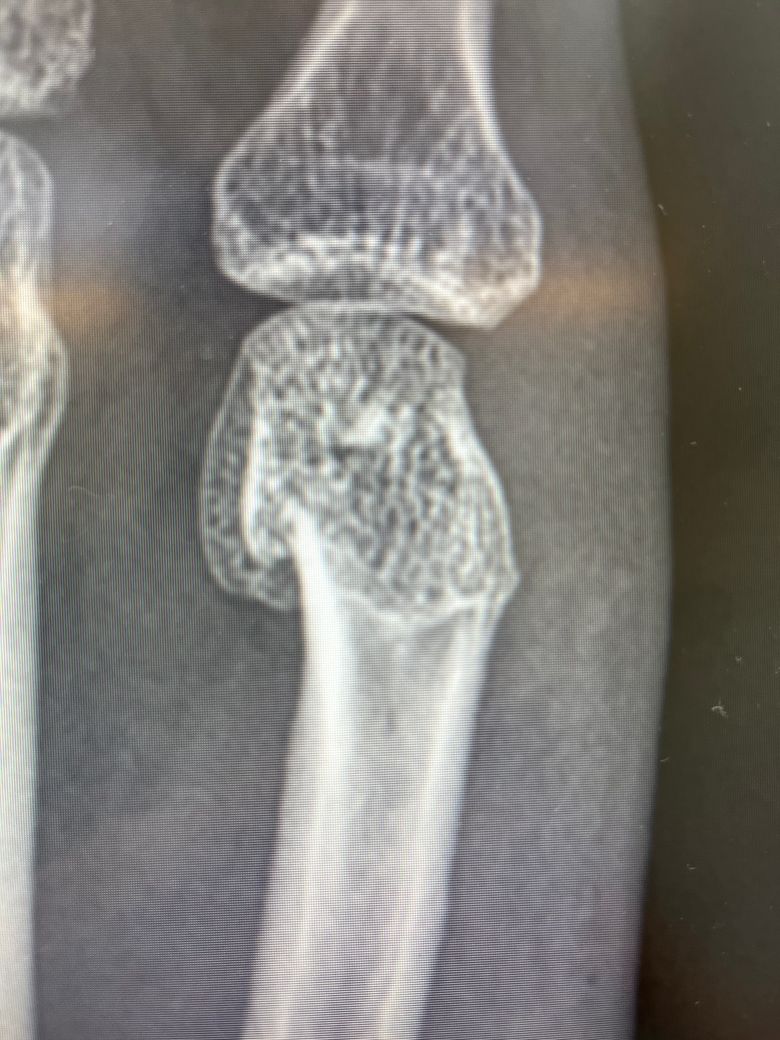

지난주 목요일 친구와 장난을 치다가 철문을 오른손 주먹으로 가격한 이후 부어올라 동네 병원을 방문했더니 복서골절이라는 진단을 받았습니다

교정치료를 진행하고 교정이 잘 되지않아 수술을 하여야 할 것 같다며 큰병원으로 가라고 이야기해주셨는데요 해당 골절의 경우 수술이 꼭 필요할까요? 통증도 별로 없고 많이 붓지도 않아 저는 최대한 깁스만으로 회복하고 싶습니다.

• 3번 째 사진

여러 각도의 사진이 필요하겠지만 정복 reduction 가능하다면 그래도 됩니다.

단지 " 교정치료를 진행하고 교정이 잘 되지않아" 라고 말씀하셨듯이 시도를 했지만 잘 되지 않아 수술을 고려하시라는 이야기를 들으신 것으로 생각이 되는데요

따라서 정황상 진료를 보셨던 선생님의 소견을 따라 수술을 고려하시는 것이 좋을 것 같습니다.